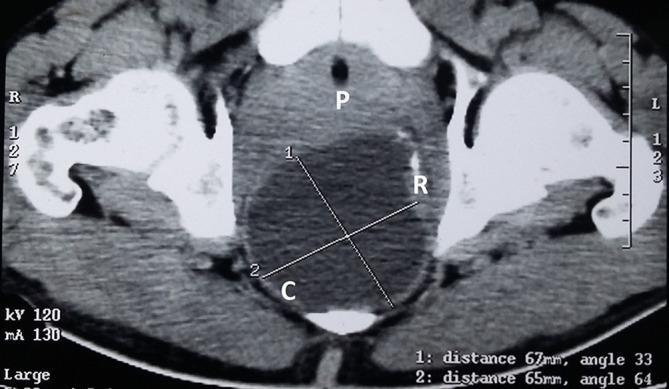

Tailgut duplication cyst (retro-rectal cystic hamartoma) is a rare congenital developmental lesion arising from post-natal primitive gut remnants. Tailgut cysts are found more commonly in middle-aged females. It may be asymptomatic or symptomatic in complicated cases. Major differentials include epidermoid cyst, dermoid cyst and anterior meningocele. Unfortunately no radiological sign can specifically diagnose it and surgical resection and histopathology remain the cornerstone for diagnosis. Here we present a case of symptomatic tailgut duplication cyst in an adult male.

尾肠重复囊肿(直肠后囊性错构瘤)是一种罕见的先天性发育性病变,由出生后原始肠管残余物引起。尾肠囊肿在中年女性中更为常见。它可能无症状,也可能在复杂病例中有症状。主要鉴别诊断包括表皮样囊肿、皮样囊肿和前脑膨出。不幸的是,没有影像学征象能特异性诊断该病,手术切除和组织病理学检查仍是诊断的基石。在此,我们报告一例成年男性有症状的尾肠重复囊肿病例。